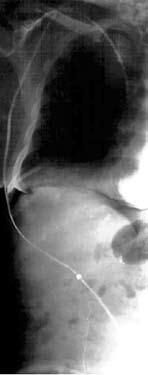

Рис. 86. Зонд Блэйкмора. А – общий вид; Б – схема постановки

При интенсивном кровотечении, когда невозможно найти участок с нарушенной стенкой вены, при тяжелом состоянии больного показана постановка зонда Блэйкмора (с его установки и следует начинать лечение в большинстве случаев, так как эндоскопический гемостаз пока возможен не во всех учреждениях, да и в ночное время может не быть нужного специалиста и соответствующего технического обеспечения, а, кроме того, эндоскопический гемостаз на высоте кровотечения может быть технически невыполним, так как кровь будет заливать оптику). Эффективность метода достигает 85 %, а количество рецидивов – 50 % (рис. 86).

Баллонная тампонада зоны кровотечения позволяет временно его остановить, после этого проводится гемостатическая терапия и восполняется кровопотеря. Через сутки давление в баллонах снижают. При остановке кровотечения могут быть предприняты попытки эндоскопической профилактики кровотечения путем паравазальной склеротерапии (при этом эффективность метода составляет около 90 %, а рецидивы кровотечения возникают почти в 30 % случаев) или эндоскопического лигирования вен пищевода (рис. 85; рис. 87).